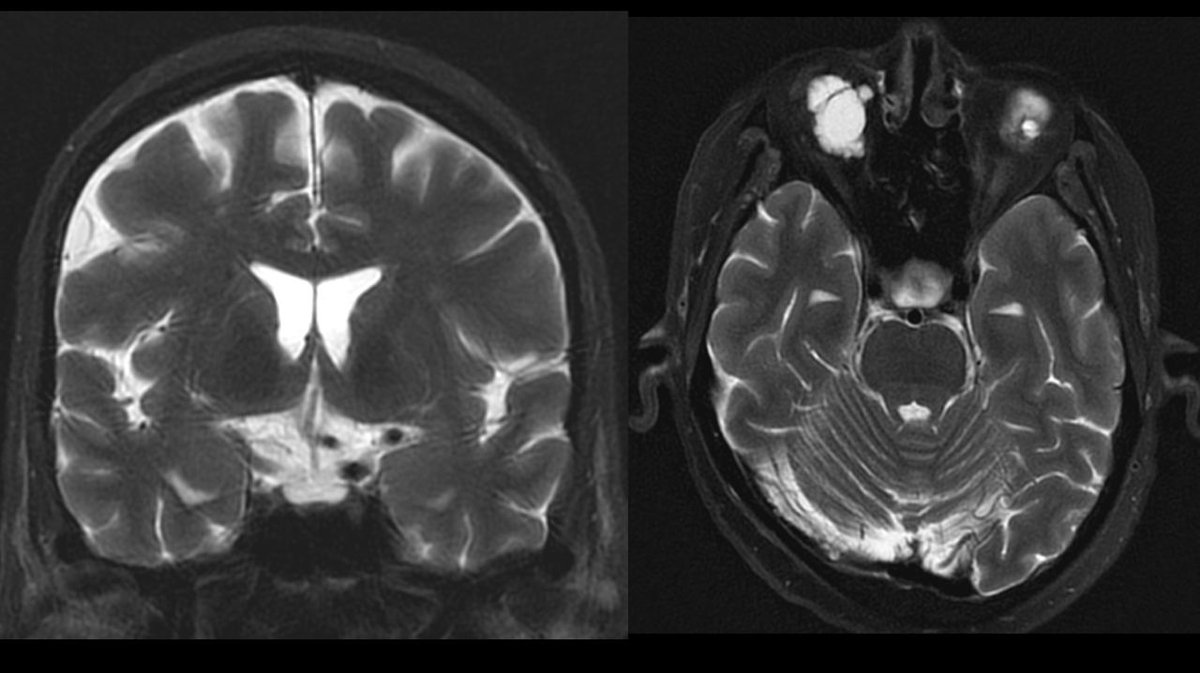

One of the largest malpractice awards ever just dropped: "Hospital on the hook for $120M jury verdict after residents miss signs of stroke on CT" radiologybusiness.com/topics/healthc… Always interested in learning from diagnostic error, I looked up the court documents.🧵pt1 (names redacted)

Should an LP be used in headache? Discussion at #ACEP23 as practice in USA changing to use CTA rather than LP after plain CT. Seems to be a good idea to avoid ‘admission for LP’ - but increase radiology load and probably needs experienced reporter.